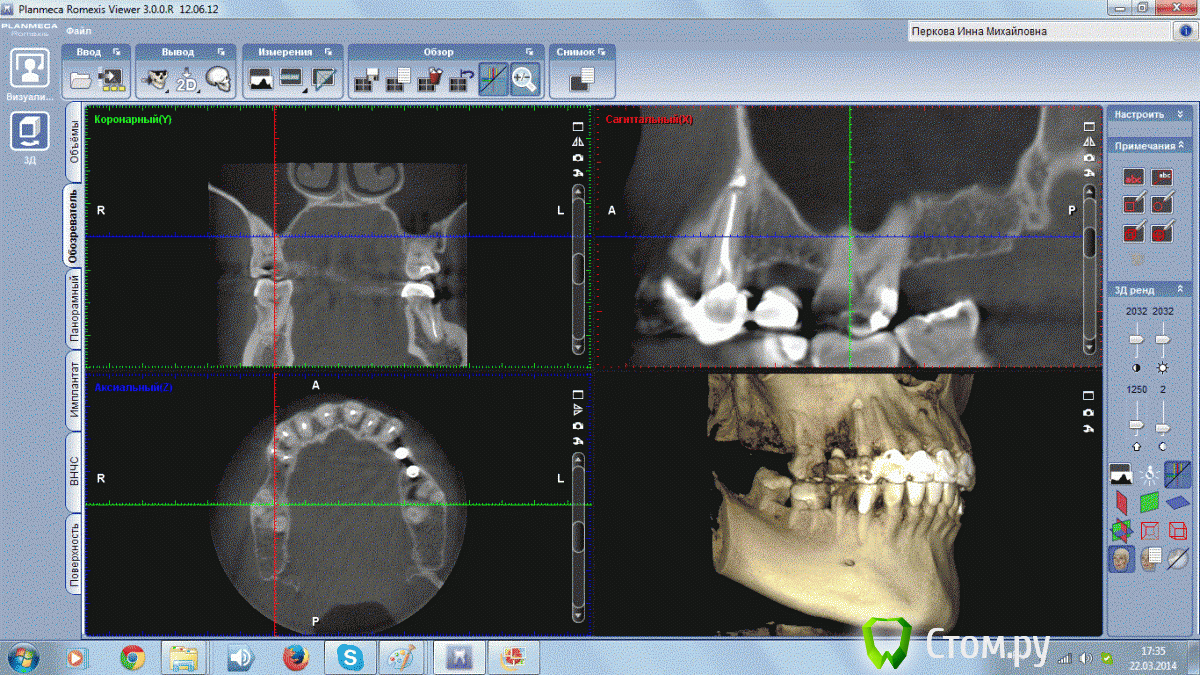

Инна Михайловна Опубликовано 22 марта, 2014 Поделиться Опубликовано 22 марта, 2014 (изменено) Добрый День!,У меня на 1 зубе обнаружили на КТ гранулему, но обнаружили уже после лечения канала. Долечен ли канал до верхушки? И посмотрите пожалуйста состояние остальных зубиков. Старая металлокерамика слетела, хочу делать новое протезирование. Изменено 22 марта, 2014 пользователем Инна Михайловна Ссылка на комментарий

Инна Михайловна Опубликовано 22 марта, 2014 Автор Поделиться Опубликовано 22 марта, 2014 Спасибо большое за скорый ответ! А на остальных зубах у корней небольшие затемнения? Эти зубы не надо перелечивать? Ссылка на комментарий